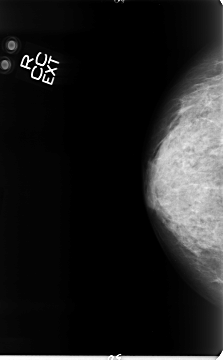

B_3062_1.LEFT_MLO

LEFT_CC LINES 4672 PIXELS_PER_LINE 2432 BITS_PER_PIXEL 12 RESOLUTION 50 OVERLAY

LEFT_MLO LINES 4632 PIXELS_PER_LINE 2776 BITS_PER_PIXEL 12 RESOLUTION 50 OVERLAY